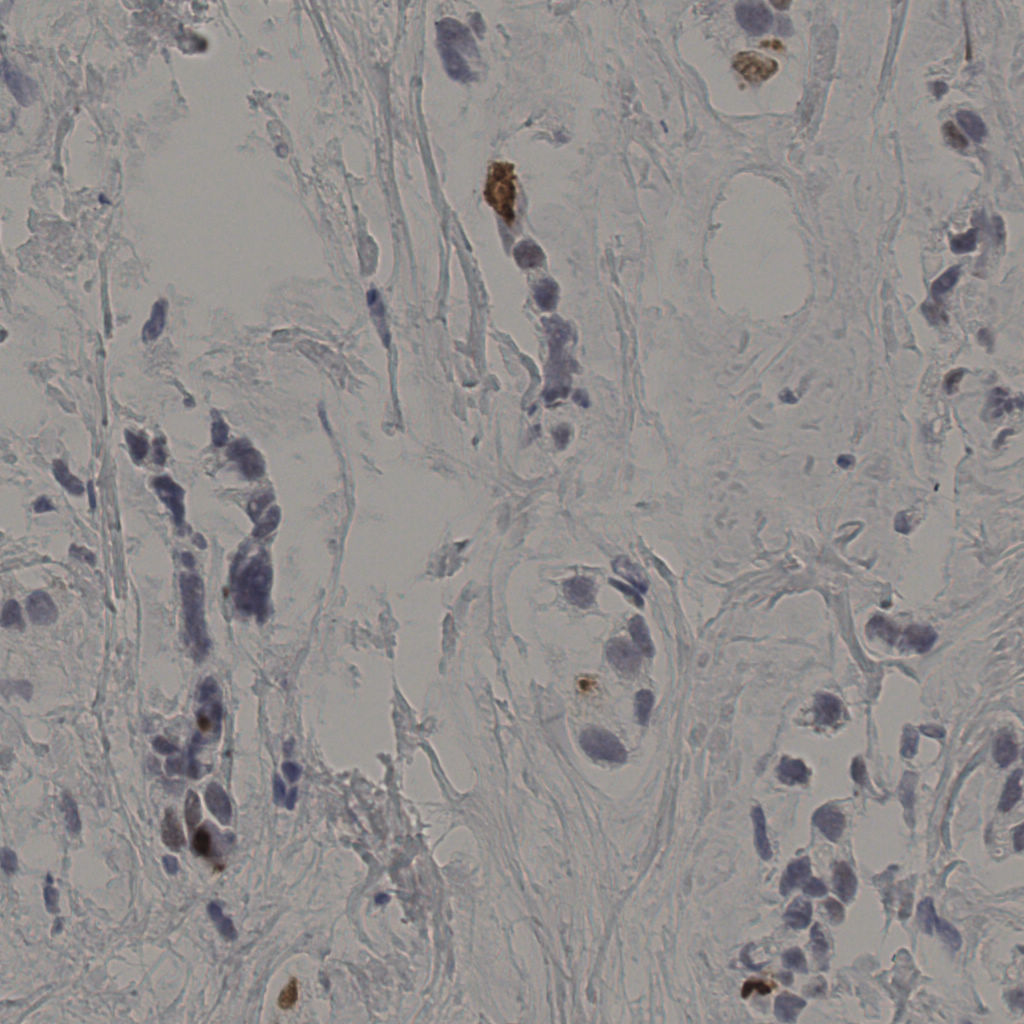

缩略图

标记后

标记前